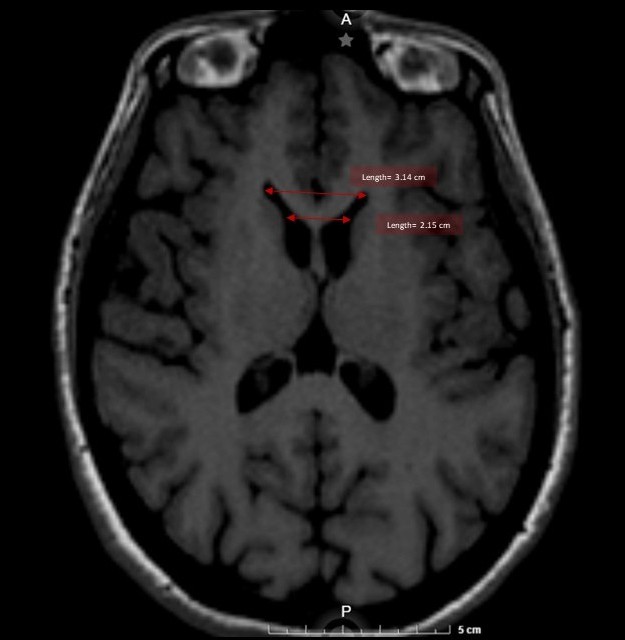

On physical examination, she exhibited motor impersistence, generalized choreiform movements, distal dystonia in the right leg, and cognitive impairment (MoCA test: 19 points). Brain MRI showed atrophy of the head of the caudate nucleus(FH/CC = 1.44; CC/IT = 0.18)(Figure 1).

Figure 1